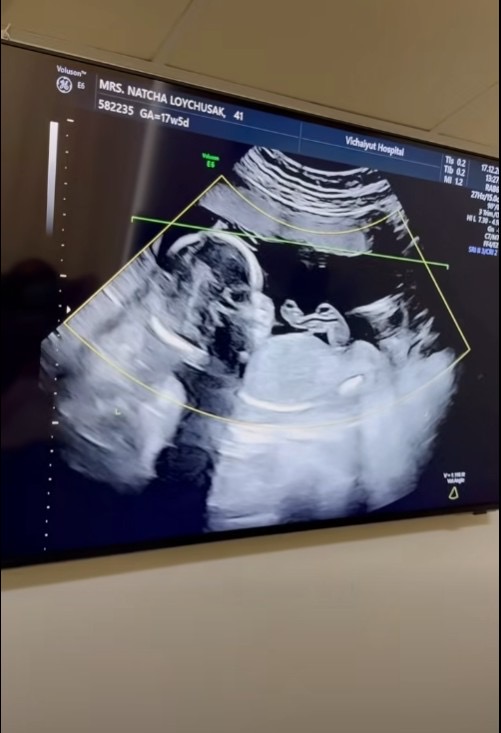

เรียกได้ว่าเป็นช่วงเวลาแห่งความสุขแบบคูณสองของครอบครัว “ลอยชูศักดิ์” เลยทีเดียว เมื่อคุณแม่คนสวยอย่าง “ครูก้อย นัชชา ลอยชูศักดิ์” ภรรยาสุดที่รักของ “เจมส์ เรืองศักดิ์ ลอยชูศักดิ์” ออกมาอัปเดตการตั้งครรภ์โชว์ท้องที่เริ่มป่องอย่างเห็นได้ชัด หลังตั้งครรภ์ลูกสาวคนที่สองได้ 17 สัปดาห์ พร้อมโชว์ภาพอัลตราซาวด์ที่เผยให้เห็นว่าเบบี๋ตัวยาวสมบูรณ์สุดๆ แถมมีแววจะตัวสูงตามรอยพี่สาวอย่าง “น้องเมดา” มาติดๆ

งานนี้คนที่ตื่นเต้นไม่แพ้พ่อแม่ก็คือ “น้องเมดา” ที่ตอนนี้กลายเป็นผู้ช่วยมือหนึ่ง ดูแลคุณแม่เป็นอย่างดี แถมยังเป็นคนรีเควสต์อยากมีน้องเอง หลังจากเห็นเพื่อนๆ ที่โรงเรียนมีพี่น้องกันหมด โดยเจมส์เล่าว่า พยายามให้ลูกสาวอยู่ในทุกช่วงเวลาสำคัญ ไม่ว่าจะไปพบคุณหมอหรือตอนอัลตราซาวด์ เพื่อให้เขาเกิดความผูกพันและมีส่วนร่วม เพราะบางครั้งเด็กในวัยนี้อาจเข้าใจผิดได้ว่าแม่จะแบ่งปันความรักให้น้องมากกว่าเขาแต่ตอนนี้เขารู้สึกว่าตัวเองเป็นส่วนหนึ่งของการมาของน้อง ทำให้เขารักและอยากช่วยดูแลน้องตั้งแต่อยู่ในท้อง